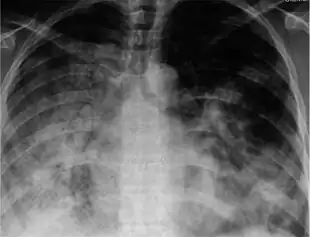

Symptomatic infections are usually mild and limited to the upper respiratory tract, but progression to pneumonia is relatively common. Pneumonia may be caused by the primary viral infection or by a secondary bacterial infection. Primary pneumonia is characterized by rapid progression of fever, cough, labored breathing, and low oxygen levels that cause bluish skin. It is especially common among those who have an underlying cardiovascular disease such as rheumatic heart disease. Secondary pneumonia typically has a period of improvement in symptoms for 1–3 weeks[29] followed by recurrent fever, sputum production, and fluid buildup in the lungs,[24] but can also occur just a few days after influenza symptoms appear.[29] About a third of primary pneumonia cases are followed by secondary pneumonia, which is most frequently caused by the bacteria Streptococcus pneumoniae and Staphylococcus aureus.[23][24]